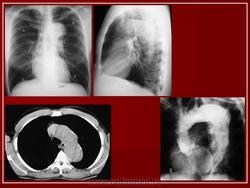

Расслоение аорты.